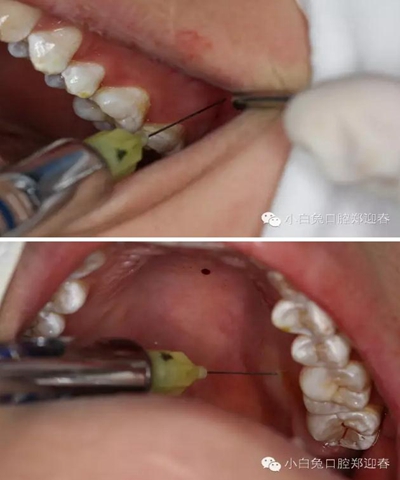

同期準備拔除28,28頰側(cè)牙尖萌出,余牙面均被牙齦覆蓋。

首先,必蘭0.5ml行上牙槽神經(jīng)和腭前神經(jīng)阻滯麻醉。

采用創(chuàng)面不縫合的切瓣方式

充分暴露牙冠部分

微創(chuàng)牙挺挺出28